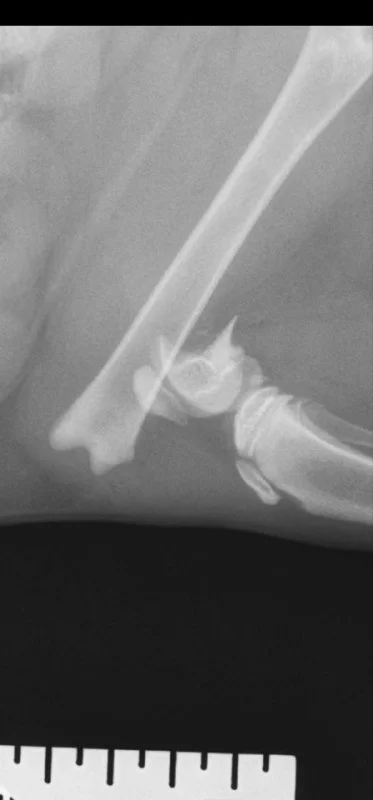

Всем здоровья, может быть кто подскажет куда поехать вот это котику исправить . В клинике где сделали рентген нам заломили более 400 евро . Котик уличный .

Cyprus Animals 2023-11-02 14:27 UTC photo

No text content